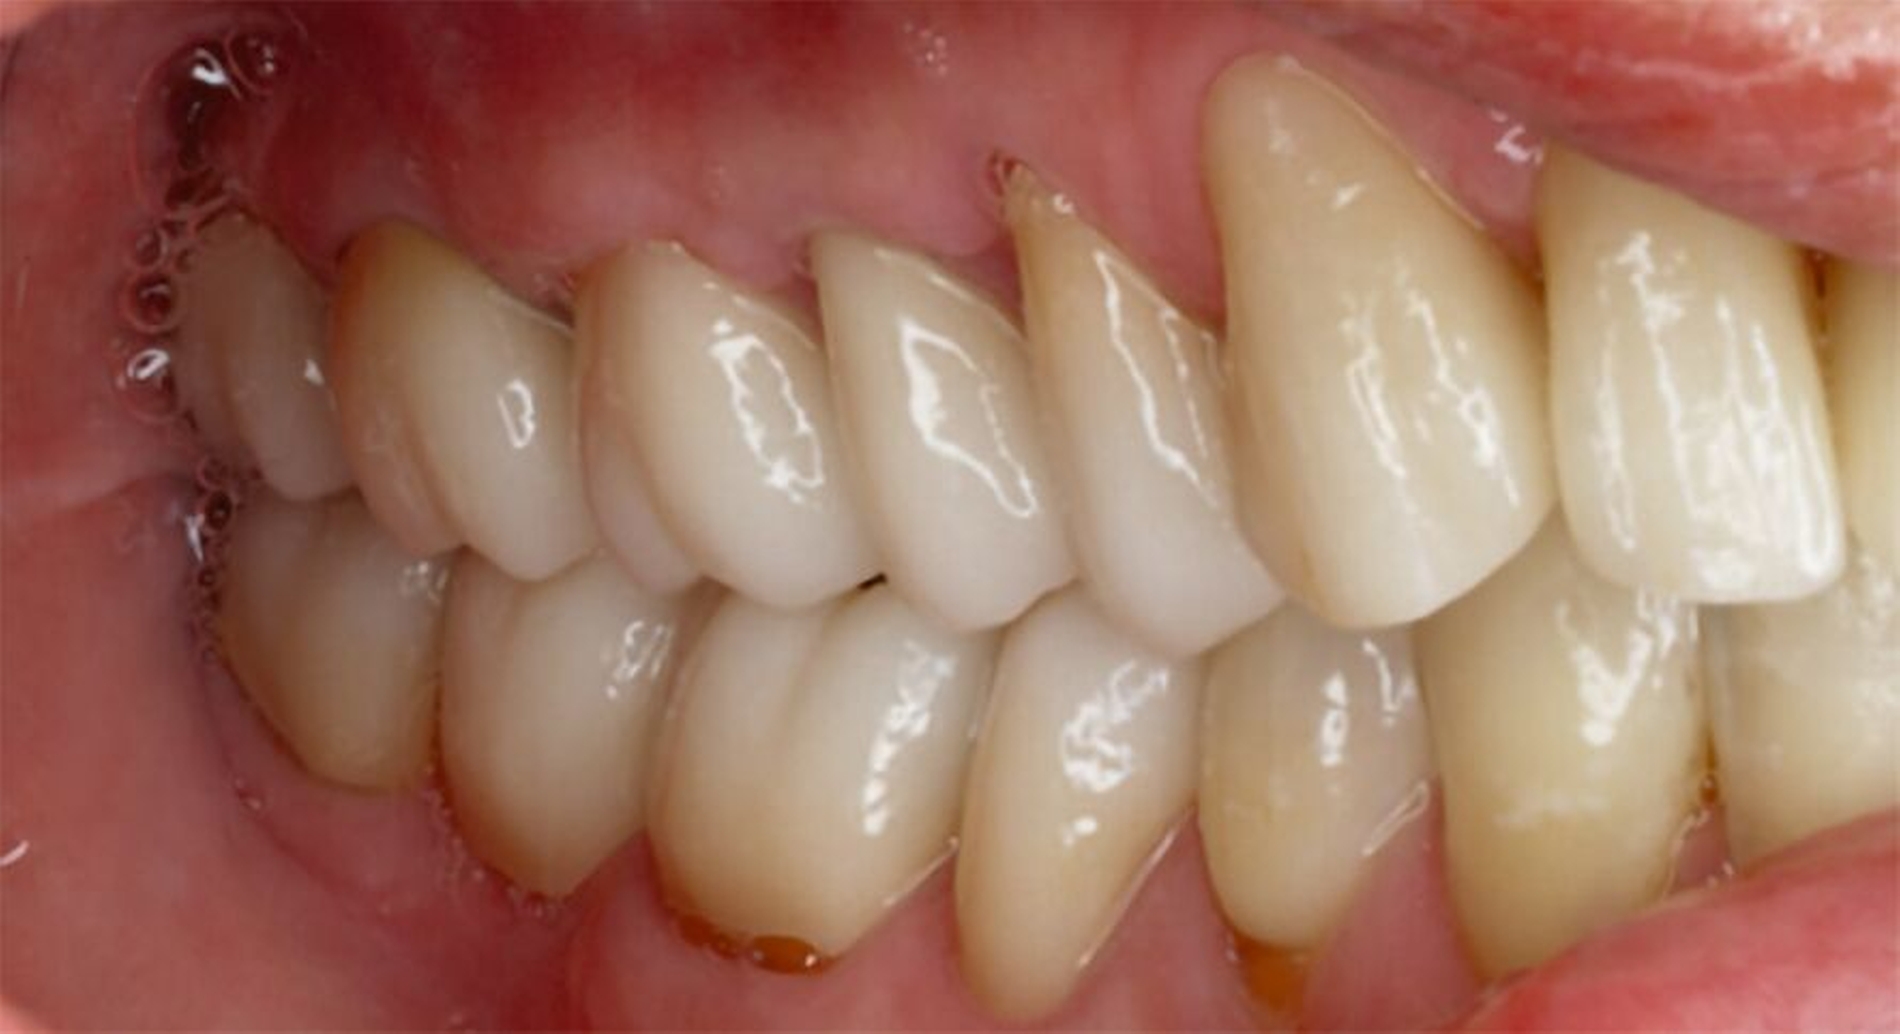

Tabelle 1 zeigt das entsprechende Befundschema mit den Taschentiefen mesial und distal, den Lockerungsgraden und den Sensibilitätsüberprüfungen mittels Kältespray (ViPr). Die Ruheschwebelage wurde mithilfe des Zielinsky-Zirkels auf 2 mm bestimmt. Die Nonokklusion im Seitenzahnbereich konnte auf circa 1,5 mm bemessen werden. Tabelle 2 spiegelt das entsprechende Okklusionsprotokoll wider. Das Okklusionsprofil wird auch in den Abbildungen 3a bis 3c deutlich.

Die anschließenden Verlaufskontrollen zeigten klinisch stabile Verhältnisse. Der prothetische Behandlungsaufwand betrug etwa acht Monate inklusive Planung, Begutachtung, Durchführung und Inkorporation des Zahnersatzes. In den Folgeterminen wurde der Patientin noch eine Aufbissschiene für den Unterkiefer eingegliedert, um Schäden durch etwaigen Schlafbruxismus vorzubeugen [Macedo et al., 2007]. Für die Nachsorge empfiehlt sich ein halbjährliches Kontrollintervall. Die erfolgte Okklusionskorrektur im Seitenzahnbereich wird in Abbildung 11 deutlich.